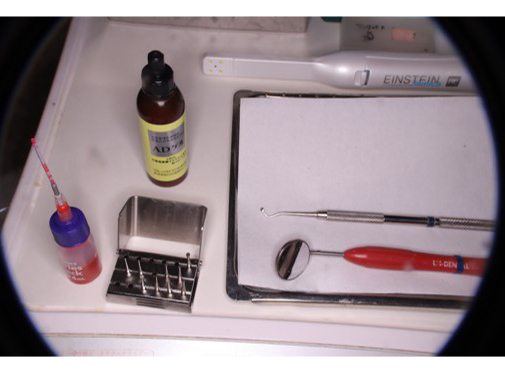

実際に使用する器具・薬剤

POINT低速回転のエンジン、手用切削器具でむし歯を除去

精密むし歯治療では、歯を削る量を最小限に抑えることを重視します。むし歯に感染した部分は軟らかくなるため、低速で回転する器具や「エキスカベーター」というスプーン状の手用器具を使い分け、指先の感覚で硬さを確かめながら丁寧に取り除きます。

これにより、健全な歯質を削りすぎるリスクを防ぎ、歯への負担を最小限に抑えることが可能です。痛みの軽減や神経の保護にも繋がり、歯の寿命を延ばすための大切な工程です。

低速回転のエンジン

手用切削器具